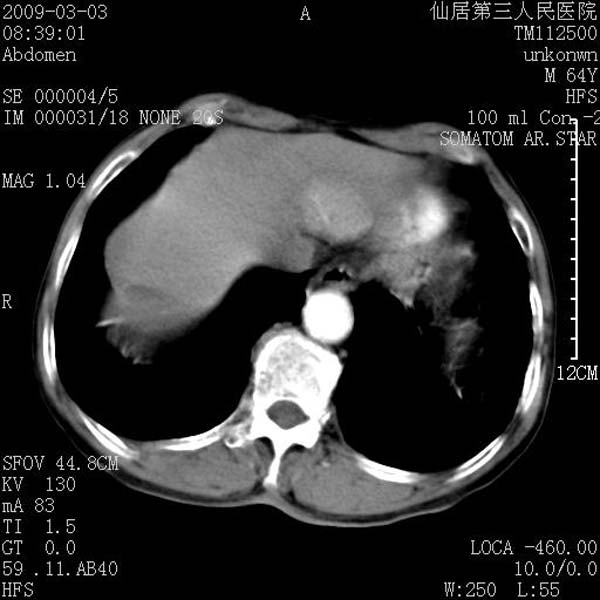

标题: CT18469:男性,64y,体检B超示肝脏低回声肿块,有胃溃疡手术 [打印本页]

患者,男性,64y,体检b超示肝脏低回声肿块,有胃溃疡手术史。

考虑----胃肠道间质瘤可能性大

从平扫及增强的特点来看,支持肝脏腺瘤并出血。

考虑胃间质瘤可能性大。

胃肠道间质瘤!

ct值呢?感觉没强化,象囊性。

考虑肝静脉韧带裂区良性占位性病变(囊肿?)。

考虑肝囊肿并出血可能性大.

考虑高密度囊肿可能性大